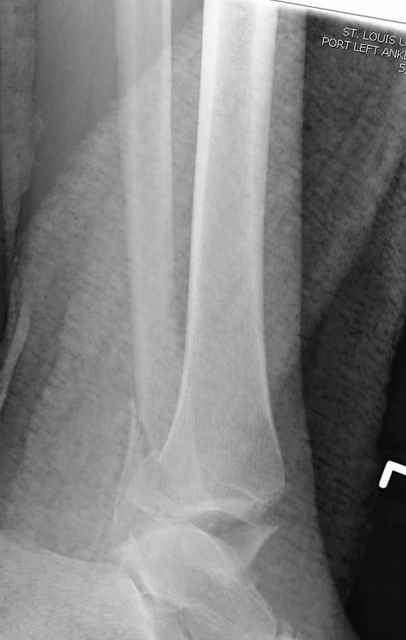

Pilon fracture:

-Появляется ориентир и остов, на чем можно строить восстановление, почему сперва малоберцовую, впервые обьяснили и описали (Pylon type and Ankle fractures) в середине 50х Rienau и Gay.

Восстановливая длину и ротацию малоберцовой кости, затем относительно легче произвести реставрацию остальных элементов перелома дистального эпиметафиза болшеберцовой кости.

где исследования на трупах показали, что малоберцовая кость участвует в стабильности голеностопного сустава, поддерживая наклон тарана (talar tilt) за счет связок. После ознакомления работой Ramsey в ортопедию ввели термин "при переломах голеностопного сустава смещенная

таранная кость следует за малоберцовой костью" т.е. связка не рвется, а тянет таран за собой, поэтому восстановление малоберцовой кости в

первую очередь, затем остальных элементов - стал классическим при лечении данной патолгии. Латеральная колонна (столб), дистальный

конец малоберцевой кости, к нему прикрепляется латеральный суставной фрагмент дистального эпиметафиза большеберцовой кости (как на снимке)

и таранная кость, которые при репозиции малоберцовой кости репонируются автоматически.